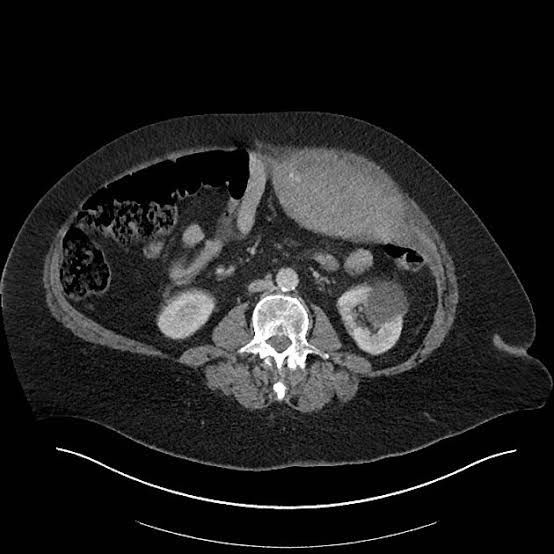

Your rectus sheath is a connective tissue that supports your abdominal muscles. A rectus sheath hematoma can occur when any bleeding from your epigastric arteries spreads into and builds up in your abdomen. Most rectus sheath hematomas clear up on their own and don't require medical treatment